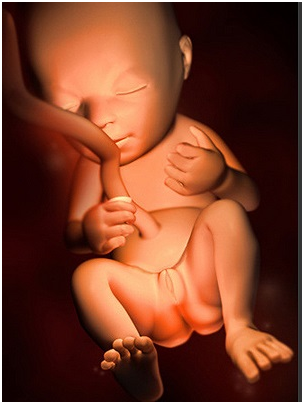

怀孕第14周祝贺你,你的肚肚就要显露出来了!宝宝身体的所有基本构造也已经形成,尽管它们很小,...

怀孕第14周祝贺你,你的肚肚就要显露出来了!宝宝身体的所有基本构造也已经形成,尽管它们很小,... -

怀孕第15周现在你需要做一次产前诊断了,15~18周之间是做产前诊断的最佳时期;怀孕改变了你...

怀孕第15周现在你需要做一次产前诊断了,15~18周之间是做产前诊断的最佳时期;怀孕改变了你... -

怀孕第12周现在胎儿身体的雏形已经发育完成了,你的脸和脖子上可能会不同程度地出现黄褐斑,腹部...

怀孕第12周现在胎儿身体的雏形已经发育完成了,你的脸和脖子上可能会不同程度地出现黄褐斑,腹部... -

怀孕第13周胎儿脸部更加清晰了,肚子开始变大,妊娠趋于稳定,妊娠反应消失,食欲也很不错。这时...

怀孕第13周胎儿脸部更加清晰了,肚子开始变大,妊娠趋于稳定,妊娠反应消失,食欲也很不错。这时... -

怀孕第16周现在你可以感到胎动啦,可别忘了把你第一次感到胎动的时间记下来哦!一定要抓住这段时...

怀孕第16周现在你可以感到胎动啦,可别忘了把你第一次感到胎动的时间记下来哦!一定要抓住这段时... -